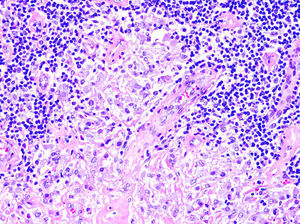

El patrón histológico puede ser liquenoide, similar a la MF, o nodular, simulando el linfoma del centro folicular (fig. 1), aunque a diferencia de aquel no observaremos células bcl6+ fuera de los centros germinales reactivos6,33. Ocasionalmente aparecen grupos de células CD30+33. Es característico que los histiocitos del infiltrado, solitarios o agrupados formando granulomas epitelioides, muestren abundante citoplasma granular y basófilo (fig. 2), que se corresponde con el depósito intracelular del aluminio de la vacuna, en los casos en los que este es el elemento implicado.